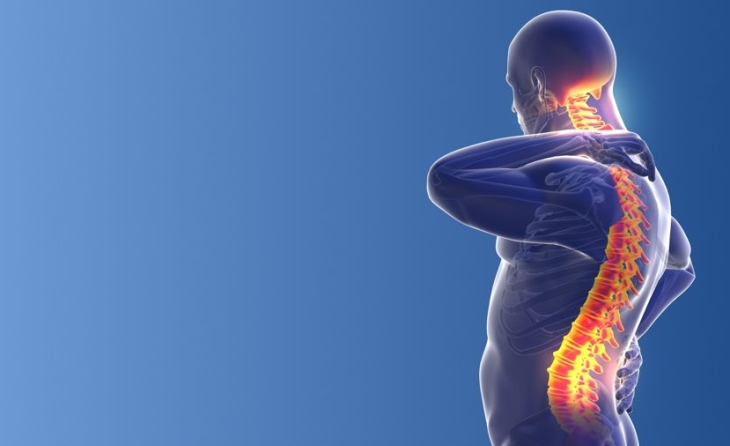

Τι είναι η περιφερική νευρική διέγερση

Η διέγερση των περιφερικών νεύρων αποτελεί μια προηγμένη τεχνική αντιμετώπισης του χρόνιου ανθεκτικού νευροπαθητικού πόνου περιορισμένης κατανομής. Αφορά σε εμφύτευση πολύ λεπτών ηλεκτροδίων κάτω από το δέρμα, κοντά στο πάσχον νεύρο, τα οποία μέσω ηλεκτρικής διέγερσης που χορηγείται από τη γεννήτρια της συσκευής, τροποποιούν την αντίληψη των μηνυμάτων πόνου από τον εγκέφαλο. Έτσι ο ασθενής αντιλαμβάνεται το επώδυνο ερέθισμα σαν μυρμήγκιασμα ή ήπιο καύσος. Η γεννήτρια της συσκευής εμφυτεύεται υποδορίως σε κοντινή περιοχή και οι παράμετροι της διέγερσης ρυθμίζονται μέσω εξωτερικού προγραμματιστή. Πλέον υπάρχουν και συστήματα νευροδιέγερσης, τα οποία δεν απαιτούν εμφύτευση γεννήτριας υποδορίως, και λειτουργούν μέσω ενός πομπού που επικολλάται σαν patch στο δέρμα.

Ποια σύνδρομα πόνου δύναται να αντιμετωπισθούν αποτελεσματικά με περιφερική νευρική διέγερση

- Ο πόνος από τραυματισμό περιφερικού νεύρου

- Ο πόνος μέλους φάντασμα σε ακρωτηριασμένα μέλη

- Το Σύνδρομο σύνθετου περιοχικού πόνου

- Ο επίμονος μετεγχειρητικός πόνος συγκεκριμένης και περιορισμένης κατανομής

- Η μετεγχειρητική οσφυαλγία

- Ο πόνος από περιφερικές νευραλγίες και νευροπάθειες

- Η αυχενοϊνιακή κεφαλαλγία